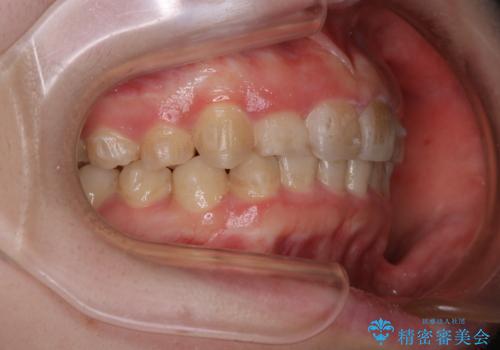

- インビザラインでのマウスピース矯正中の方で、歯の表面のステインをきれいに取りたいとのことでした。PMTC60分コースを行いました。

PMTC(保険外治療)は、毎日の歯磨きで落としきれない汚れや、コーヒ、紅茶・タバコのヤニなどの着色も除去します。目には見えない歯と歯の間・歯肉の境目・インビザライン中はアタッチメント周囲などに残っているプラーク(歯垢)もしっかり取り除きます。PMTCでは専門的な機械や材料を使用して、徹底的に汚れを除去するため、虫歯・歯周病・口臭予防などにつながります。